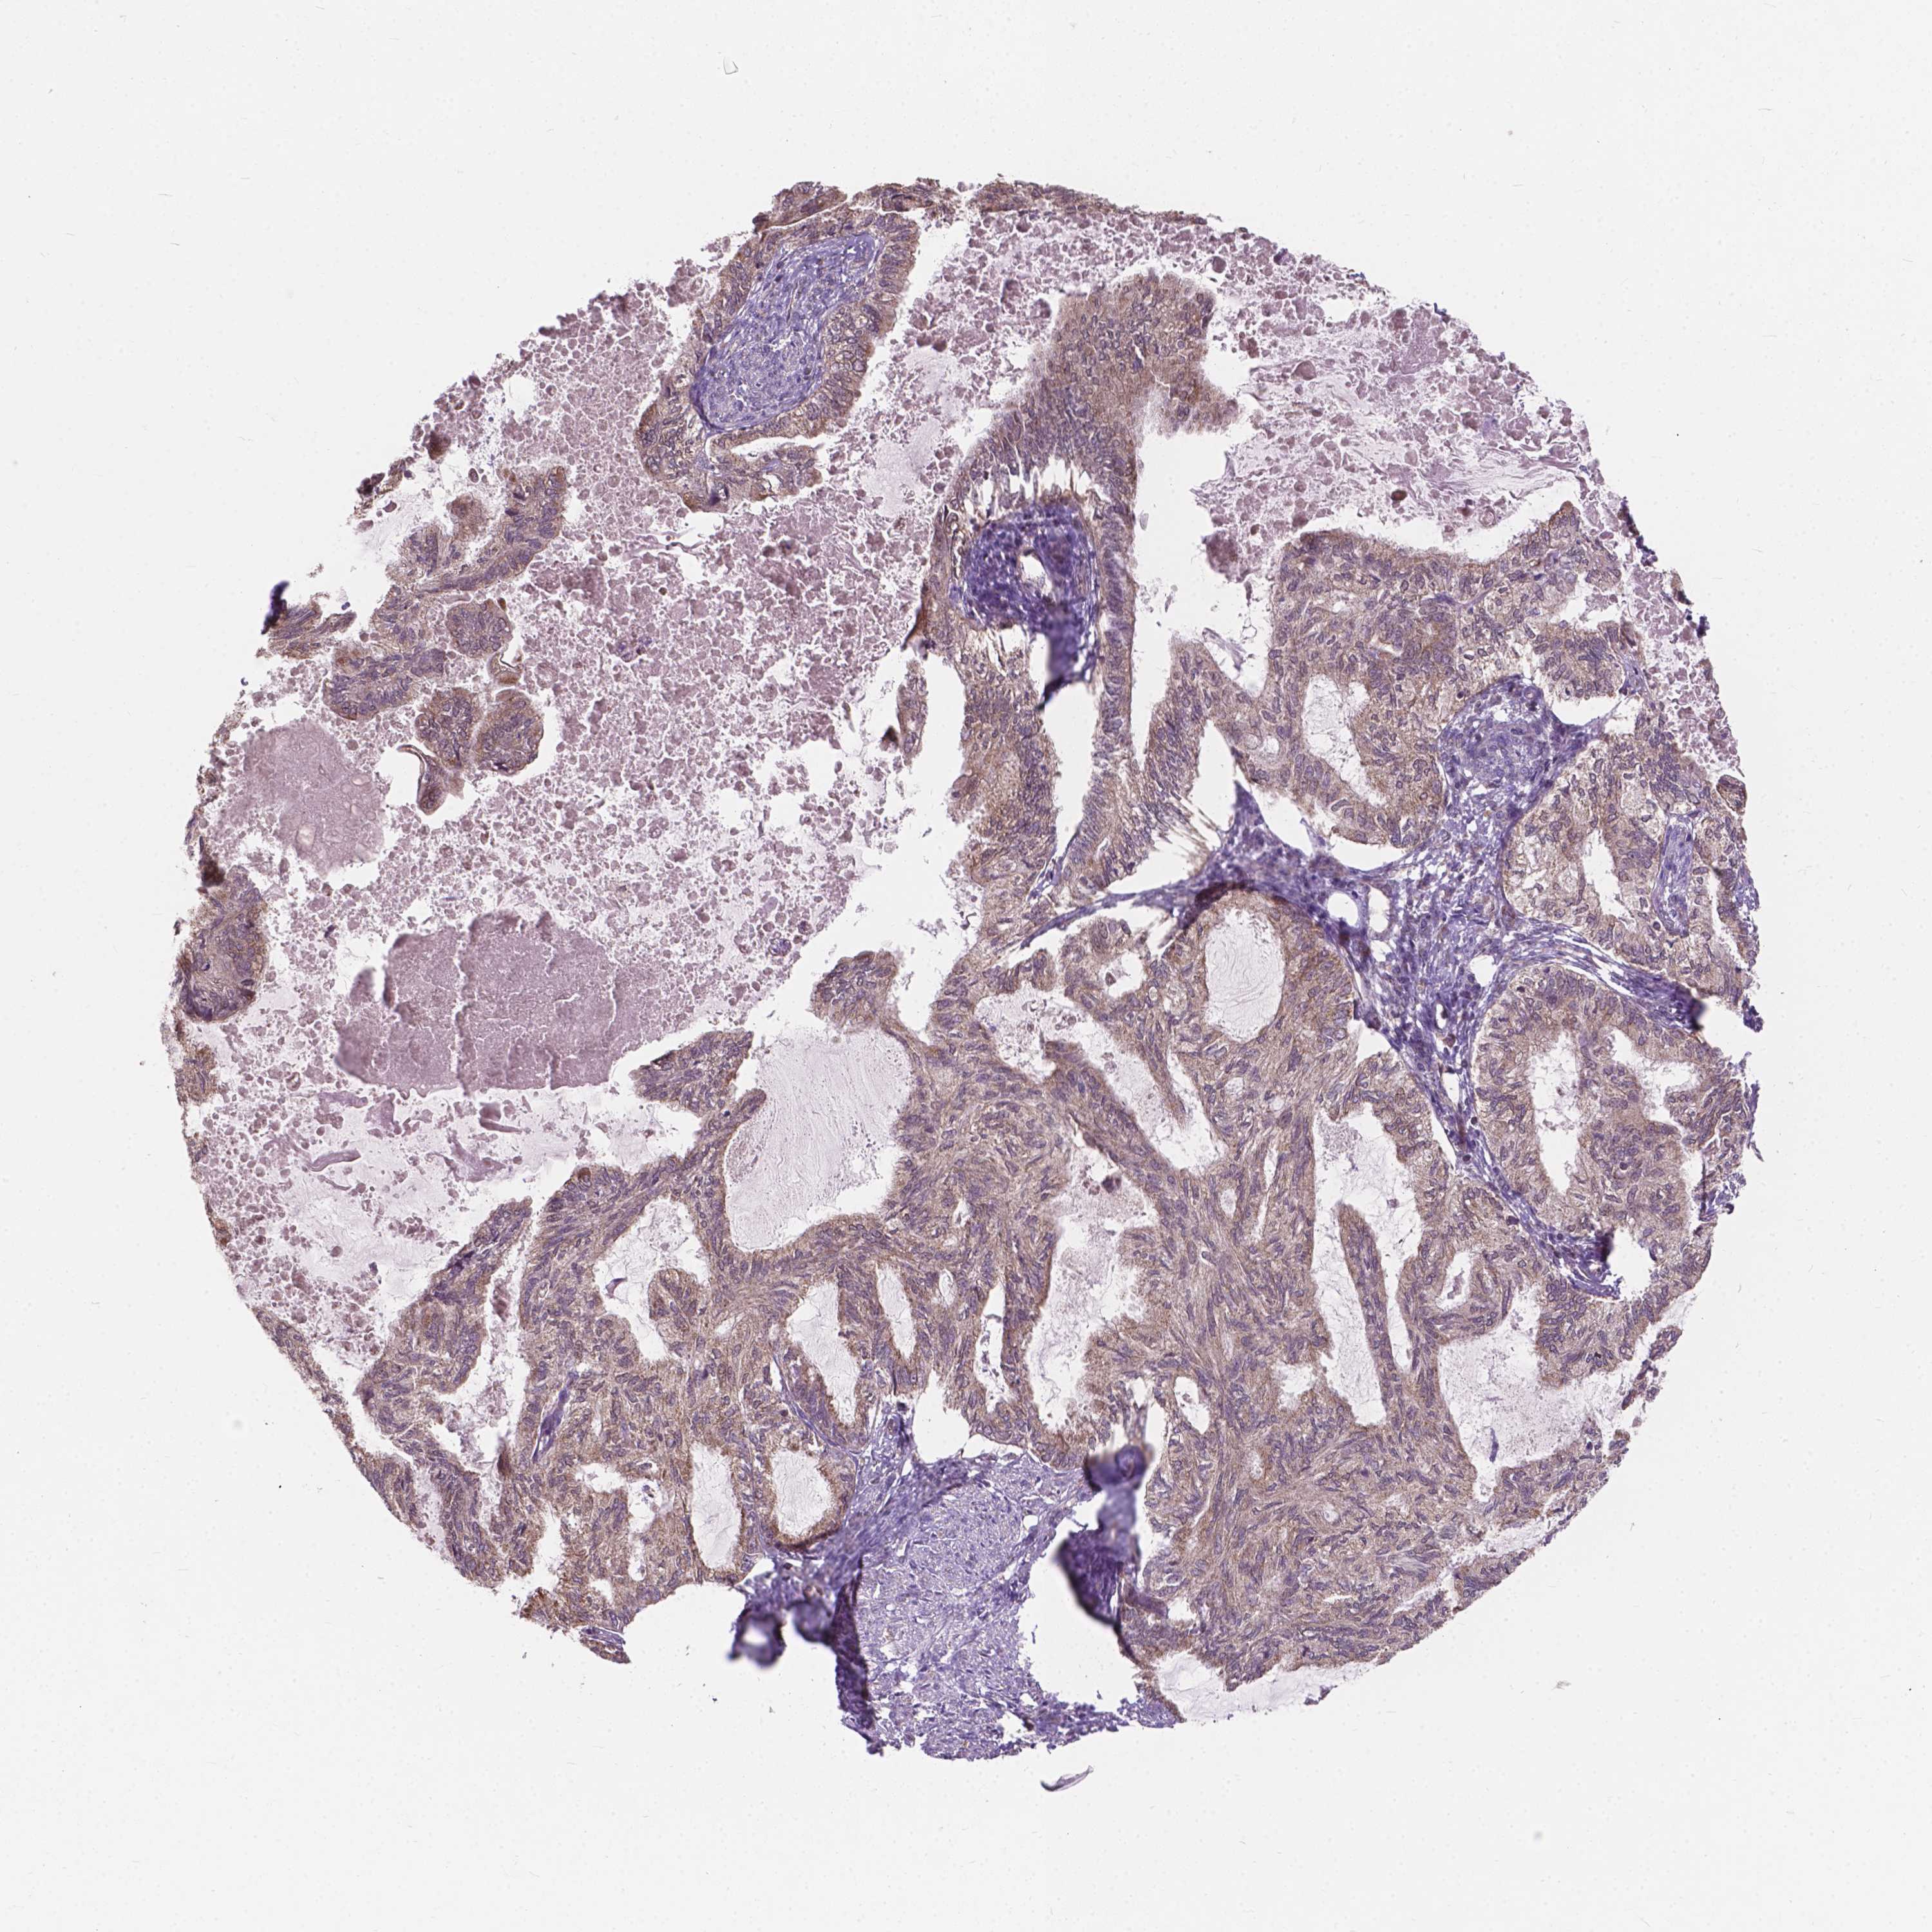

ENDOMETRIAL CANCER - Protein expressioni

A mouse-over function shows sample information and annotation data. Click on an image to view it in a full screen mode. Samples can be filtered based on level of antibody staining by selecting one or several of the following categories: high, medium, low and not detected. The assay and annotation is described here.

Note that samples used for immunohistochemistry by the Human Protein Atlas do not correspond to samples in the TCGA dataset.

Antibody stainingi

Antibody staining in the annotated cell types in the current human tissue is reported as not detected, low, medium, or high, based on conventional immunohistochemistry profiling in selected tissues. This score is based on the combination of the staining intensity and fraction of stained cells.

Each image is clickable and will lead to virtual microscopy that enables deeper exploration of all samples and also displays staining intensity scores, fraction scores and subcellular localization as well as patient and tissue information for each sample.

Antibody HPA066872

Staining

High

Medium

Low

Not detected

Intensity

Strong

Moderate

Weak

Negative

Quantity

>75%

75%-25%

<25%

None

Location

Nuclear

Cytoplasmic/membranous

Cytoplasmic/membranous,nuclear

Adenocarcinoma, NOS